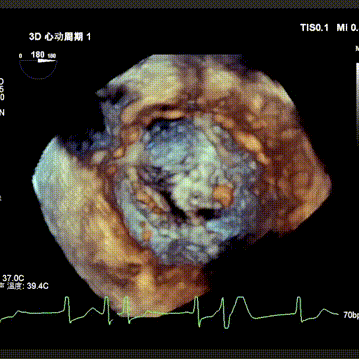

随后在超声引导下进行房间隔穿刺,最终穿刺高度约3.4cm,顺利建立经房间隔入路。而后沿成环导丝于二尖瓣环下植入固定环,通过DSA及3D超声确认固定环完全关闭且位置合适。沿股静脉送入HighLife TSMVR瓣膜,首先释放瓣膜心室端,随后牵拉输送器,超声下观察,使瓣膜心室端与固定环充分贴合,旋即保持拉力并释放瓣膜心房端,人工瓣膜脱钩,在固定环的辅助下,于二尖瓣瓣环平面完成自同轴,最后逐步撤出人工瓣膜输送系统和固定环输送系统。即刻超声评估提示二尖瓣返流完全消失,无瓣周漏,人工瓣膜植入位置理想,形态良好,跨瓣压差1mmHg;LVOT压差6mmHg,无左室流出道梗阻风险;房间隔4mm左向右分流,无即刻封堵指征。手术成功完成!

固定环位置评估

术后即刻超声评估